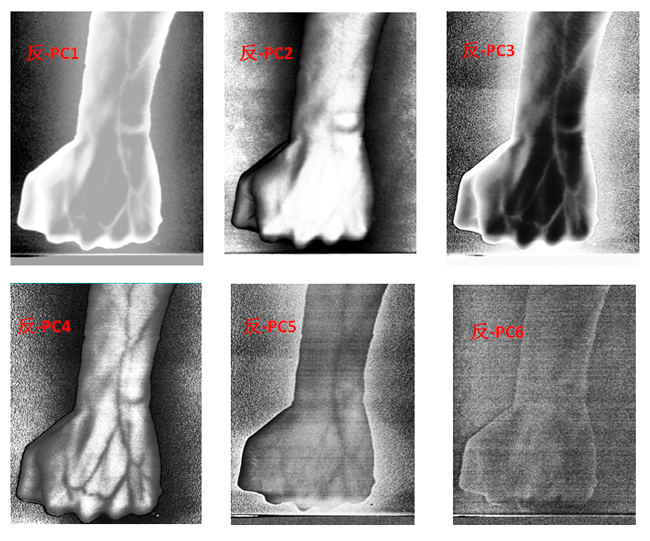

为了客观地识别手臂上的静脉,对经预处理后的高光谱数据进行主成分分析(Principal Component Analysis, PCA),去除波段之间的多余信息、将多波段的图像信息压缩到比原波段更有效的少数几个转换波段下。图9为手臂正反面经PCA变换后的前6个主成分。

图9  手臂正反两面PCA处理后的前6个主成分